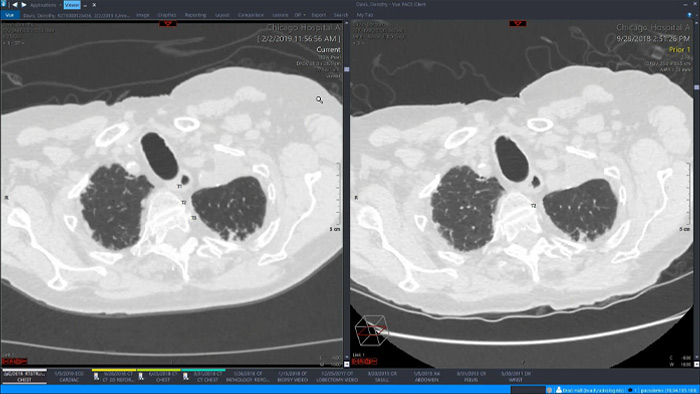

Let’s take a look at some of the immediate benefits of a unified approach. A single, unified workspace for radiology would incorporate advanced 3D post-processing and image distribution capabilities, opened in an additional viewer tab for ease.

A unified workspace would mean that users can easily launch the relevant analysis tools from among the 70+ advanced applications available across multiple clinical domains. Artificial Intelligence can play a role by automating tasks and workflows, predicting usage patterns.

An all-in-one workspace, fully integrated with the enterprise imaging platform and embedded in the diagnostic viewer, offers simple, efficient access to all needed tools across clinical domains. One-click access to advanced visualization tools – such as virtual colonoscopy, 3D processing, and spectral imaging – allows for efficient interpretation and supports diagnostic confidence.

IntelliSpace Portal

Offers advanced visualization with a robust set of tools for AI-assisted quantitative assessment and automatic results generation.